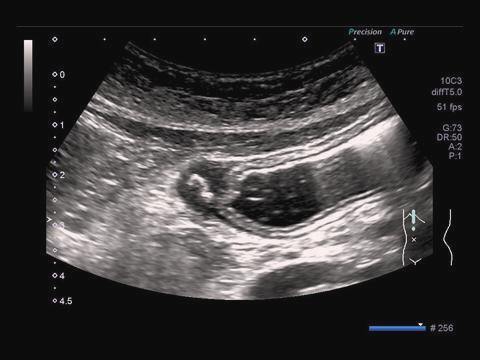

最優秀賞

鳥海 修 (公立学校共済組合関東中央病院

診断名胆嚢癌

使用機種:東芝 Aplio500

周波数:8.0 MHz

コメント(術者の一言)

病変が浅い所にあるので最初は見逃しそ

うになりました。